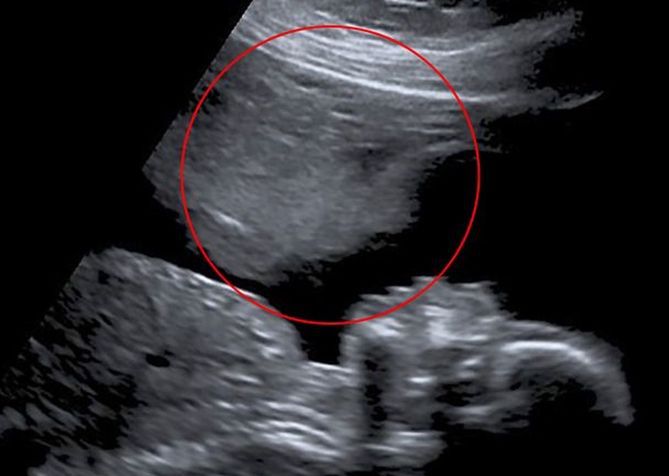

W 20. tygodniu ciąży wykonano badanie, które okazało się przełomowe. Stacey otrzymała zdjęcie USG, na którym zauważyła coś niezwykłego - kontur przypominający twarz. Dla Stacey był to znak, że nie jest sama, a ktoś "pomagał" jej przetrwać te trudne chwile.

"Myślę, że to mógł być ktoś lub coś, co nad nami czuwało" - powiedziała.